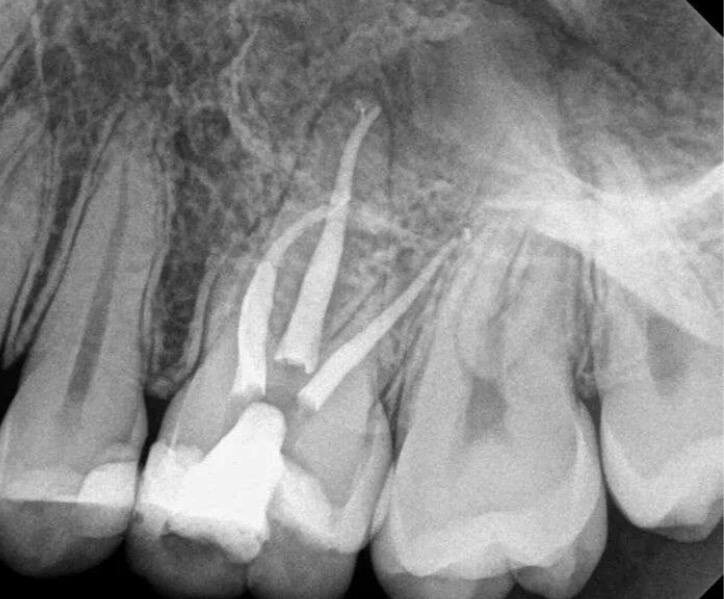

✅ Время на диагностику (КЛКТ + клинические тесты+ RVG)

✅ Два визита для медикаментозной обработки и пломбирования каналов( так же контроль на каждом этапе)

✅ Микроскоп, чтобы видеть, а не гадать 🔬